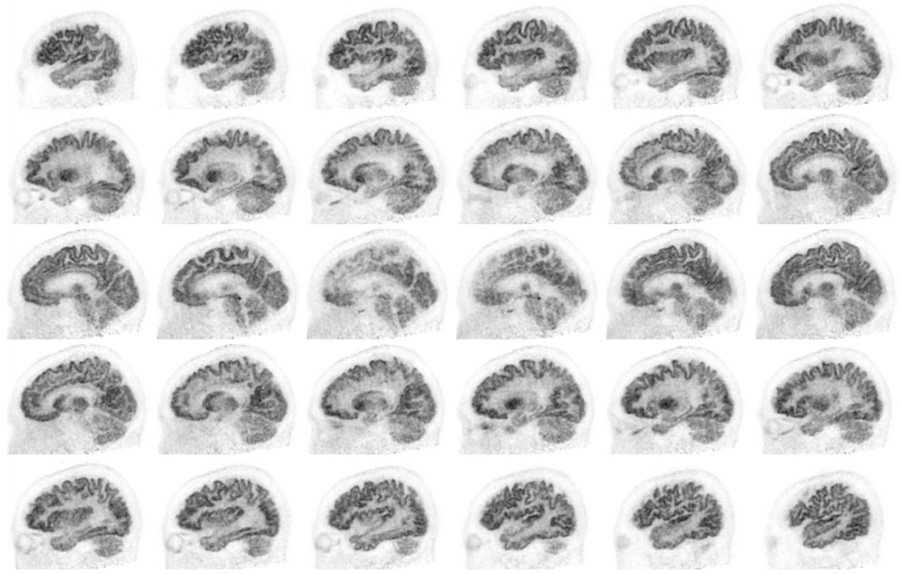

Head / Case1 : FDG

Sagittal

- Imaging protocol

- Injected dose: 2.87 MBq/kg, 18F-FDG

- Uptake time: 42 minutes

- Scan time: 30 minutes